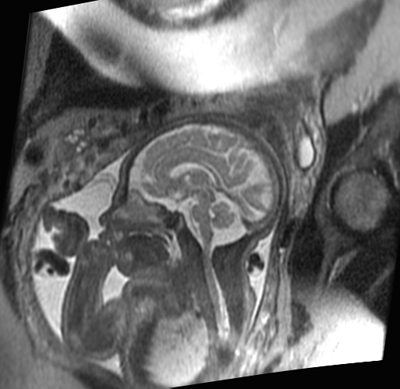

Fetal MRI Study

First, we would like to see how accurately fetal MRI detects changes in the fetus’ brain and spine during pregnancy compared to ultrasound.  While ultrasound is the most commonly used method of monitoring fetal development, its ability to detect changes in the brain is limited.  In this study, we are comparing ultrasound and MR images of fetuses to identify the situations in which fetal MRI will provide valuable clinical information not seen on ultrasound.  Studies have shown that, overall, fetal MRI is more helpful than ultrasound in evaluating the brain. We are interested in studying just how helpful fetal MRI is for different brain conditions.